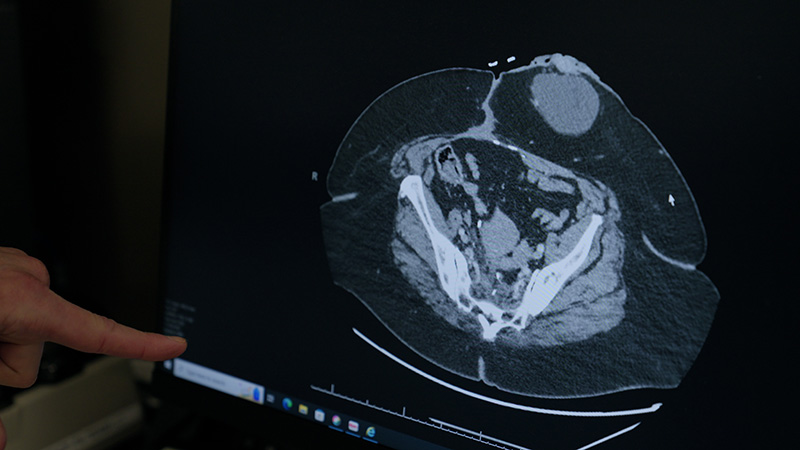

Effective colorectal cancer care begins with an accurate diagnosis. At Henry Ford Health, we offer the latest tests and procedures, so you receive the answers you need promptly. After a colorectal cancer diagnosis, our experts work together to select the best treatments for you.

We may use several tests to diagnose colorectal cancer:

Staging is the process of finding out if and how far cancer has spread (metastasized). This information is important for diagnosing colorectal cancer and determining the most effective treatments.

Staging varies depending on whether you have colon cancer, rectal cancer or anal cancer. A lower number indicates an earlier stage. Stage IV (4) colorectal cancer is advanced, meaning it has spread to distant parts of your body. At Henry Ford, our doctors have specialized expertise in metastatic colorectal cancer. We offer a range of innovative therapies for hard-to-treat cancer that helps people live longer.